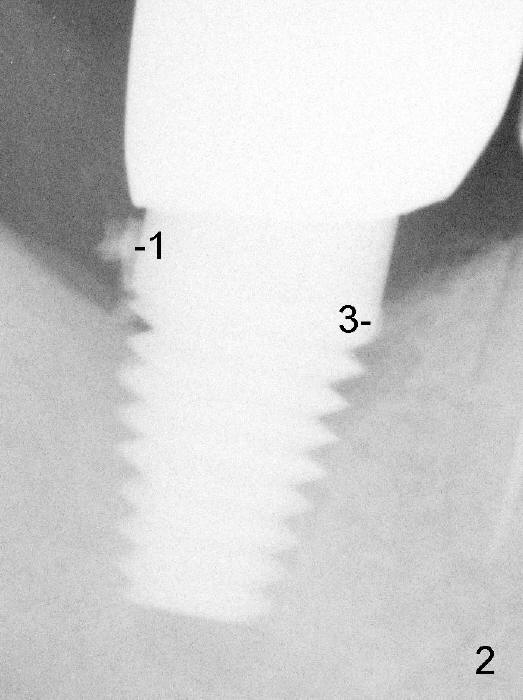

Four months post implantation, a Zirconia crown is cemented with Temp Bond. Two months later, the patient returns for recall. Bitewing shows 3 pieces of residual cement (Fig.1: #1,2,3) . Due to the thick distal gingiva (Fig.1 <), initial effort results in partial removal of the distal cement (Fig.2 (PA): #1). The shallow cement in the mesial aspect is apparently removed, whereas the deep one remains untouched (Fig.2: #3). Further removal is done before discharge without X-ray confirmation.